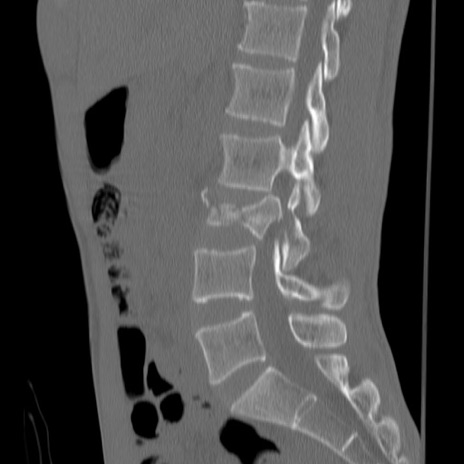

症例3 腰椎CT(矢状断像)

【症例】30歳代男性

【主訴】腰痛

【現病歴】本日旅行先で観光中に、友人と衝突し転倒し受傷。

【身体所見】麻痺なし、右下腿内側前面外側、左下腿内側に知覚鈍麻・しびれ

異常所見と診断は?

腰椎CT